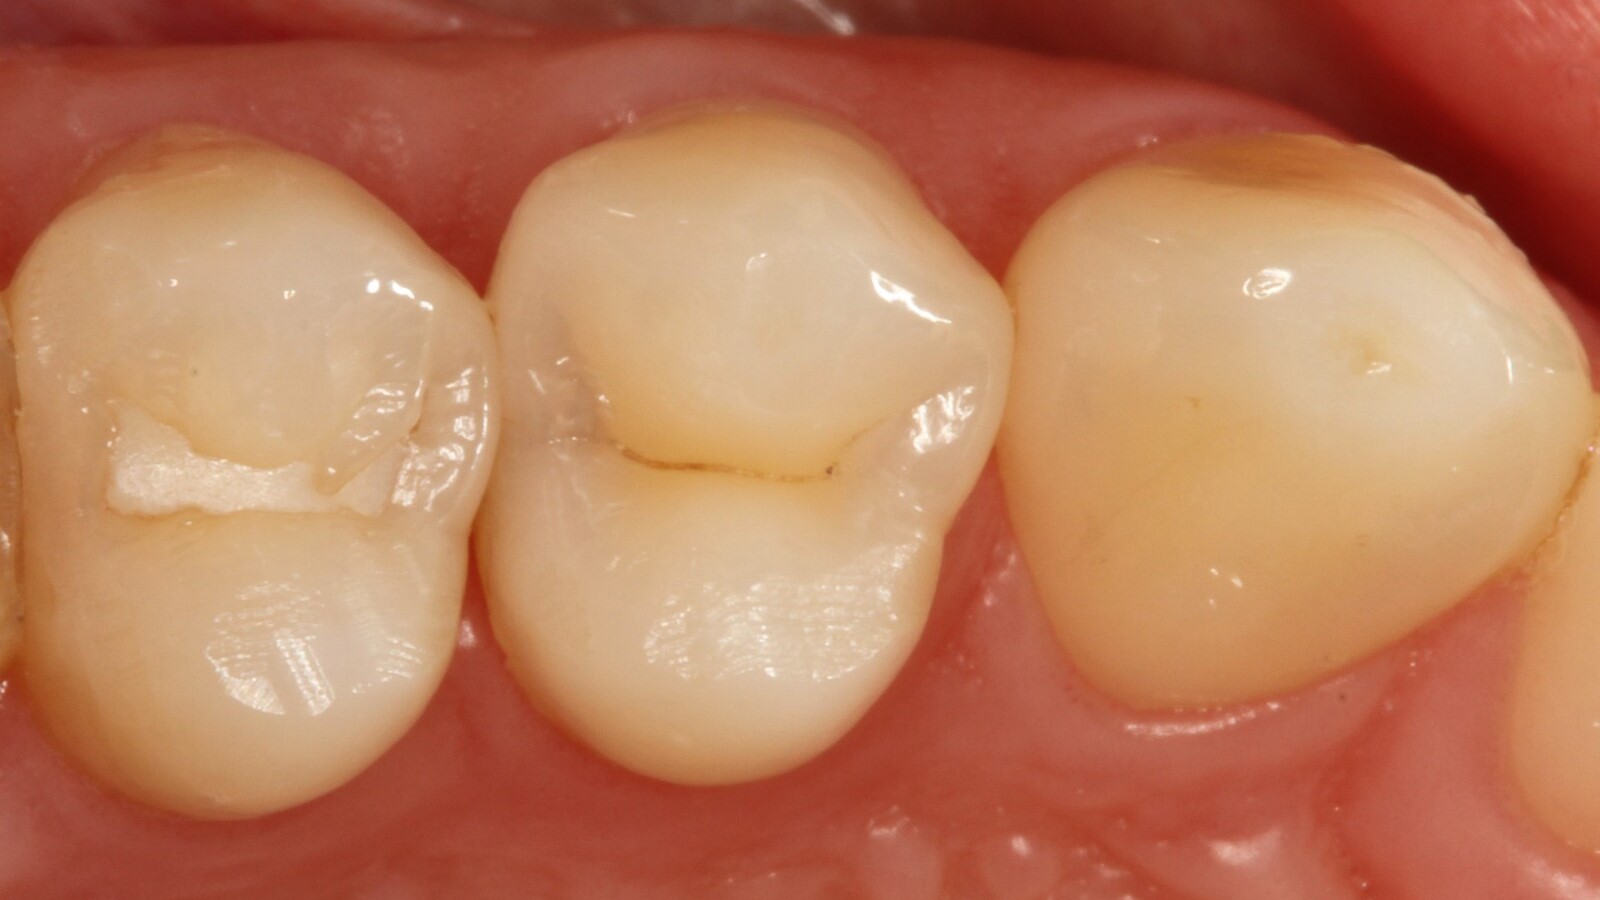

Le professeur Ernst a d'abord identifié les caries non visibles et a ouvert la lésion carieuse pour montrer le problème au patient (Fig. 1-2). Il a ensuite excavé la carie, préparé la cavité et placé une matrice sectionnelle (Fig. 3) avant de sceller la cavité avec de l'adhésif (Fig. 4). En une seule étape, il a rempli la cavité avec Venus Bulk Flow ONE (Fig. 5). Une fois la restauration terminée, le Pr Ernst l'a polie (Fig. 6) et a pris une radiographie de contrôle, qui montre également l'excellente radiopacité de Venus Bulk Flow ONE (Fig. 7).